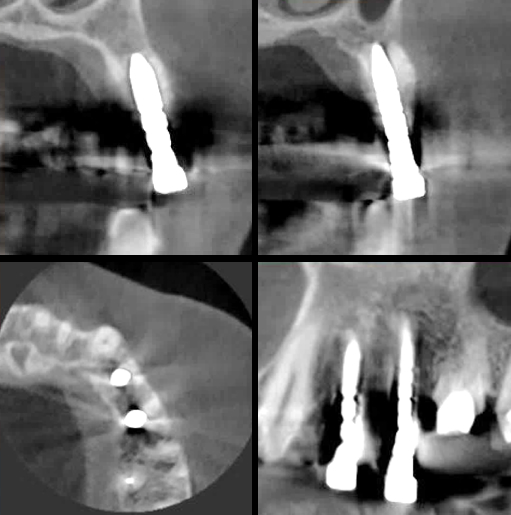

インプラント埋入前のCTによる確認

インプラント